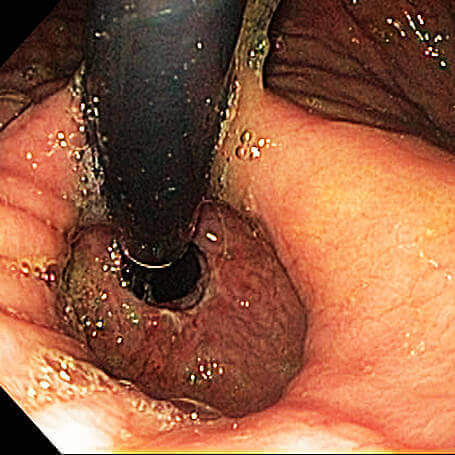

Classificação endoscópica para esofagite Classificação de Los Angeles:

Grau C – Soluções de continuidade da mucosa contíguas entre o topo de duas (ou mais) pregas, porém envolvendo menos que 75% da circunferência do esôfago;

Grau D – Soluções de continuidade envolvendo mais de 75% da circunferência do esôfago;